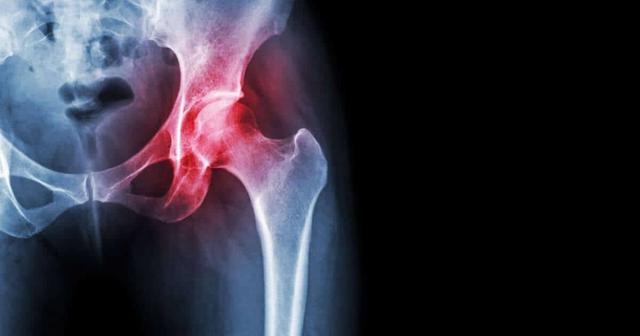

Ursachen für Hüftschmerzen mit Ausstrahlung ins Bein können verschiedene Ursachen haben. Eine häufige Ursache ist die Abnutzung und Verschleißerscheinungen am Hüftgelenk, auch bekannt als Hüftarthrose. Diese tritt meistens im fortgeschrittenen Alter auf, kann aber auch jüngere Menschen betreffen. Dabei nutzt sich der Gelenksknorpel ab und die Gleitschicht wird zerstört, was zu starken Schmerzen und Bewegungseinschränkungen führt. Neben altersbedingter Abnutzung können auch Verletzungen am Gelenk, Unfälle, angeborene Fehlstellungen, Stoffwechselerkrankungen und Fehl- oder Überbelastung zur Entstehung von Hüftarthrose beitragen.

Auch Probleme mit dem Iliosakralgelenk oder den Bandscheiben können Schmerzen verursachen, die ins Bein ausstrahlen. Die häufigste Ursache für Hüftschmerzen ist jedoch Abnutzung und Verschleiß am Hüftgelenk, auch bekannt als Hüftarthrose. Diese tritt meistens im fortgeschrittenen Alter auf, kann aber auch jüngere Menschen betreffen. Neben altersbedingtem Verschleiß können Verletzungen am Gelenk, Unfälle, angeborene Fehlstellungen, Stoffwechselerkrankungen und Fehl- und Überbelastung zu Hüftschmerzen führen.

Hüftschmerzen mit Ausstrahlung ins Bein können verschiedene Ursachen haben und den Alltag der Betroffenen erheblich belasten. Das Hüftgelenk ist eines der größten Gelenke im menschlichen Körper und besteht aus der Hüftgelenkspfanne und dem Oberschenkelkopf. Es ist ein Kugelgelenk, das sich in der Leistenregion zwischen Beckenknochen und Oberschenkelhals befindet.

Das Hüftgelenk wird von einer Gelenkskapsel, Muskeln, Sehnen und Schleimbeuteln umgeben. Der Gelenksknorpel überzieht das Hüftgelenk und sorgt für eine reibungslose Bewegung. Wenn Probleme im Hüftgelenk auftreten, können sie Schmerzen verursachen, die ins Bein ausstrahlen.

Die häufigste Ursache für Hüftschmerzen ist jedoch Abnutzung und Verschleiß am Hüftgelenk, auch als Hüftarthrose bekannt. Dies tritt meistens im fortgeschrittenen Alter auf, kann aber auch jüngere Menschen betreffen. Neben der altersbedingten Abnutzung können Verletzungen, Unfälle, angeborene Fehlstellungen, Stoffwechselerkrankungen und Überbelastung zu Hüftgelenksarthrose führen.